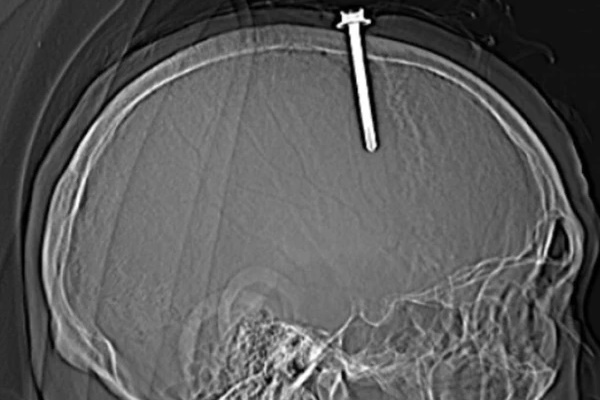

Hình ảnh cây đinh đâm xuyên vào hộp sọ bệnh nhân. Ảnh: BVĐK Thanh Hóa

Qua thăm khám lâm sàng và kết quả chụp cắt lớp vi tính sọ não cho thấy bệnh nhân có vết thương sọ não, vết thương xoang tĩnh mạch dọc trên do dị vật kim loại cắm vào vùng đỉnh bên trái, cạnh xoang tĩnh mạch dọc trên. Dị vật có đường kính 0,5 cm, chiều dài 5,1 cm.